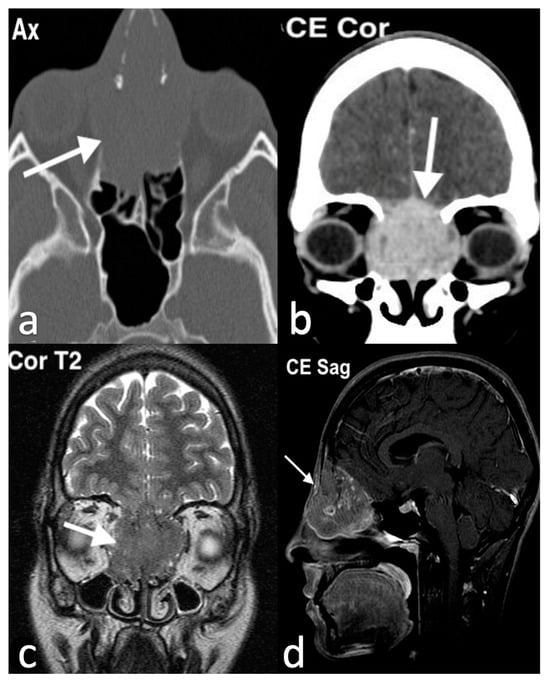

3.3.4. Melanoma

3.3.5. Rhabdomyosarcomas